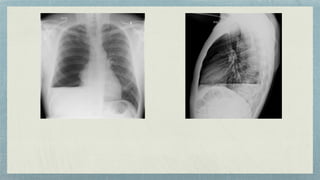

Frontal View Lateral

Stag’s Antler sign